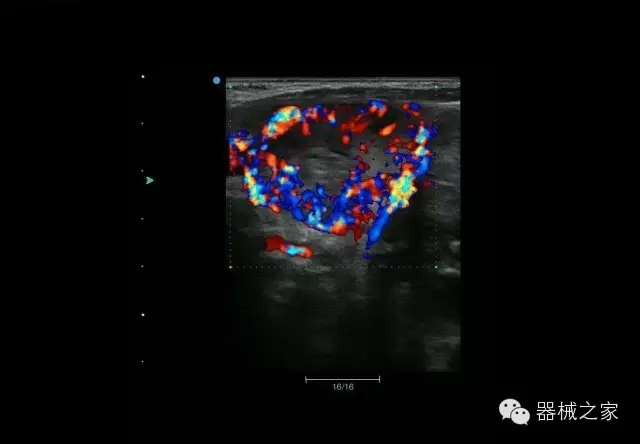

睪丸低速血流